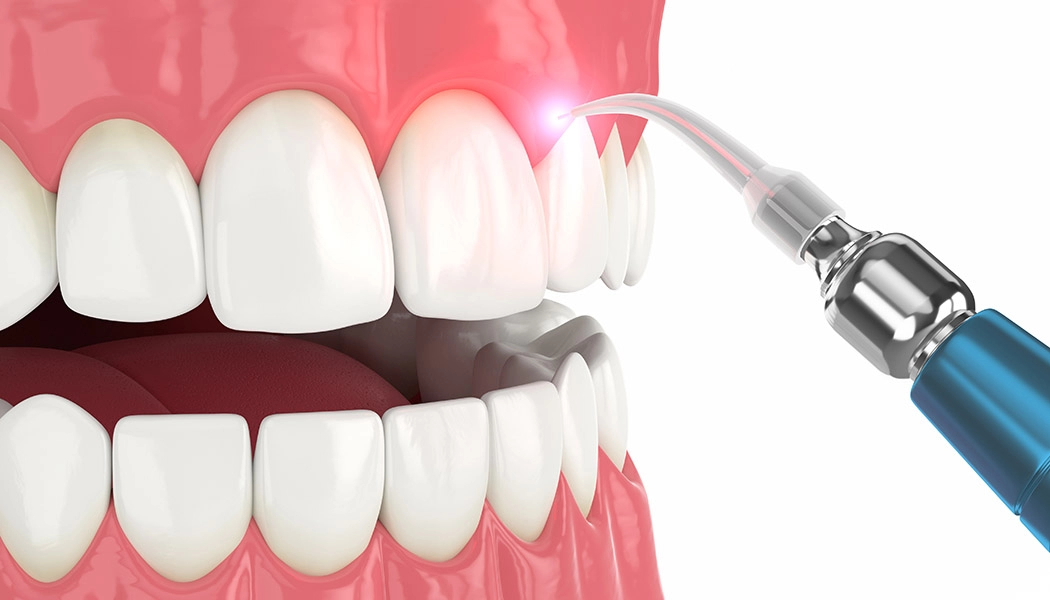

В терапевтической стоматологии лазер применяют при лечении стоматита, гингивита, герпеса, им обрабатывают пародонтальные карманы, а также используют при лечении кариеса. Для препарирования твердых тканей зуба используют, в основном, эрбиевый лазер; лазерный луч, попадая на ткани, испаряет их. Процедура практически безболезненная.